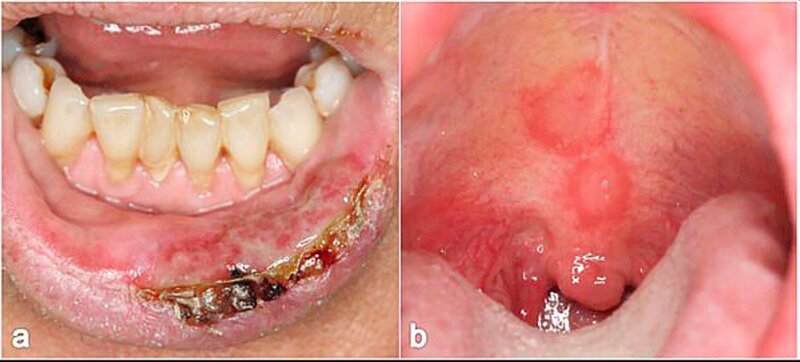

Der paraneoplastische Pemphigus ist selten. Er geht fast immer mit einer schweren Stomatitis mit ausgedehnten Erosionen der Wangenschleimhaut, Zunge und Lippen einher (Abbildungen 3e und 3f).

Larynx, Pharynx und Ösophagus können ebenfalls betroffen sein. Die Hautveränderungen sind polymorph, häufig lichenoid oder Erythema-exsudativum-multiforme- artig. Die Erkrankung ist obligat mit einer Neoplasie (meist mit hämatologischen Neoplasmen und Thymomen) assoziiert [Anhalt, 2004; Zimmermann et al., 2010].

In der Mundhöhle findet man dann am häufigsten eine desquamative Gingivitis. Erytheme und fibrinbelegte Erosionen sind auch am Gaumen, an der Innenseite der Unterlippe, der Wangenschleimhaut und der Zunge sichtbar (Abbildungen 5a und 5b). Noch intakte Blasen sieht man – wie bei den anderen bullösen AID der Mundschleimhaut – wegen der starken mechanischen Beanspruchung selten. Die Mundschleimhautläsionen heilen in aller Regel ohne Narbenbildung ab.